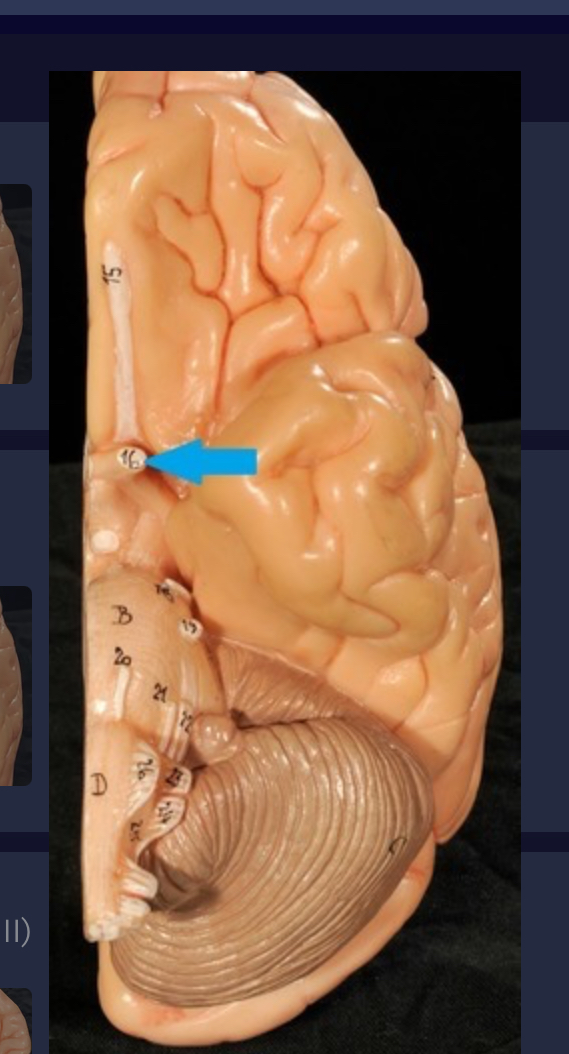

Longitudinal fissure

Cerebral cortex (gray matter)

Cerebral medulla (white matter)

Precentral gyrus

Postcentral gyrus

Central sulcus

Cerebellum

Corpus callosum

Diencephalon

Thalamus

3rd ventricle

Hypothalamus

Epithalamus (pink line)

Brain stem

Pons

Medulla oblongata

Choroid plexus of 3rd ventricle

Cerebral aqueduct (midrain)

4th ventricle

central canal